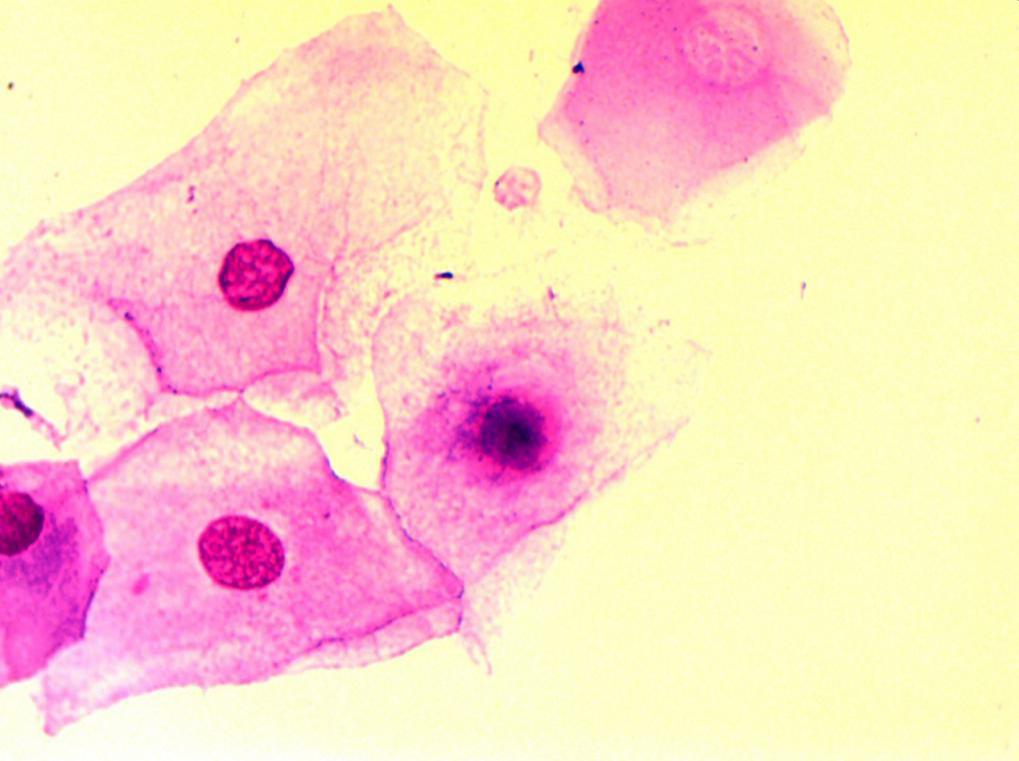

A great many white blood cells were found in the urethral swab examination indicating a urethral infection. He had already undergone a cystoscopy at home; the results showed severe infections and ulcers in his posterior urethra and bladder neck.

Staphylococcus aureus and Streptococcus were found in the prostate fluid culture, while Corynebacteria and Streptococcus were also found in the seminal fluid culture. Only by killing these causative pathogens can prostate inflammation be controlled.

On the 21st day of the treatment, fungus was found on the urethral swab and in calcification discharged in his urine. The patient had an uncomfortable feeling of ants in his urethra. After 10 days of systemic and local anti-fungus treatment, the symptoms disappeared and no fungus was evident in several following checkups. Note: some pathogens hidden in calcification can cause repeated prostate infections as they become freed by treatment-related calcification breakdown.